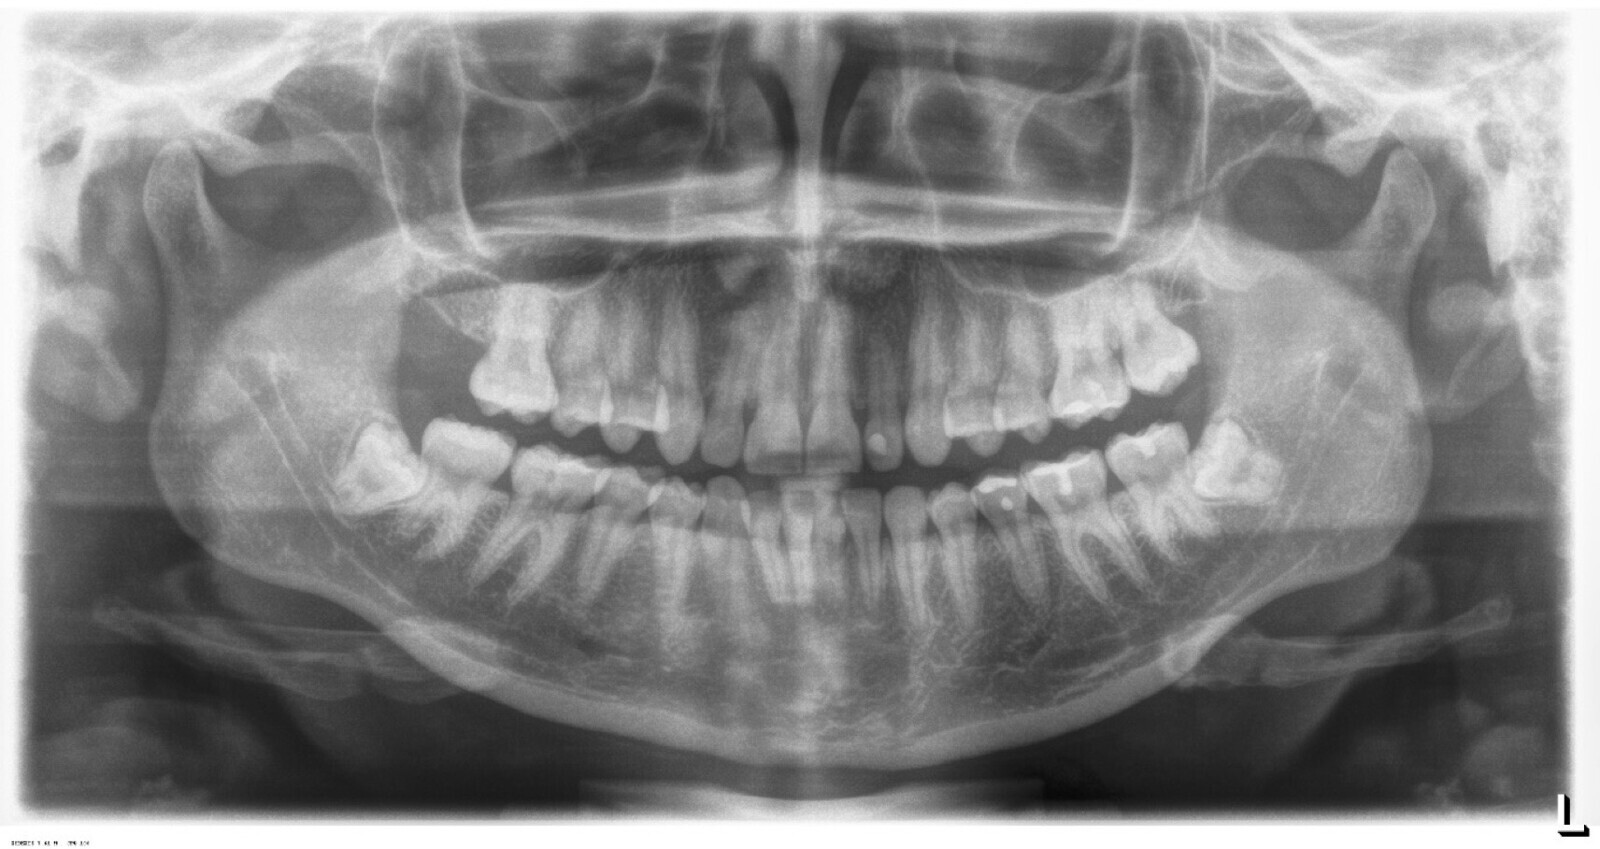

Es imprescindible conocer la ubicación de la tercera molar. Se puede emplear, adicionalmente a la evaluación clínica, herramientas radiográficas (panorámica y periapical) y tomográficas (Cone beam) para determinar la posición, grado de retención y proximidad a estructuras vecinas de riesgo como el nervio dentario inferior y así evitar lesiones (Figura 1).

Paciente de sexo femenino con 34 años, acude a consulta por molestia en la zona 38. Clínicamente se observa zona edematizada, sintomática a la palpación. Presenta apertura ligeramente limitada, crepitación unilateral en ATM (articulación temporomandibular) derecha, asintomática a la apertura o cierre articular. En el examen imagenológico se confirma impactación dental con posible compromiso distal de la pieza 37. Pieza 38 en relación IIIC (Pell-Gregory,1993) y posición mesioangulada (Winter, 1926) con aparente formación incompleta de raíces.

Figura 14. Vista radiográfica de la situación de la paciente.